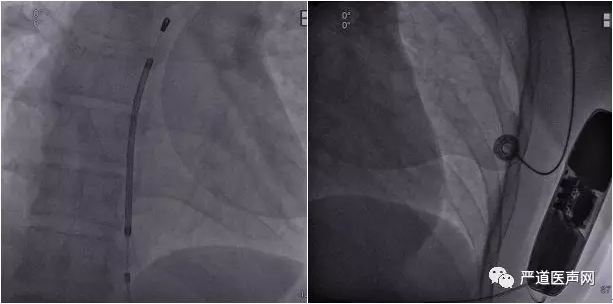

将脉冲发生器置于之前做好的囊袋中并固定,机器位置如图所示,需避免电极线翻折或牵拉,同时,应注意囊袋的大小。尺寸过大时,囊袋内容易积攒空气,导致身体运动时带动发生器产生相对活动,从而影响机器对于发生室性心律失常时R波的感知。

DFT测试:诱发后,SICD迅速感知、充电、放电治疗,患者成功恢复到窦性心律。术后X线显示脉冲起搏装置位置良好。